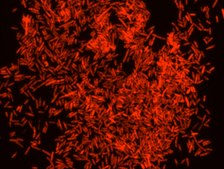

Eubacteria probe recognizes most bacteria as it is complementary to a portion

of 16S rRNA found in almost all bacteria.9,10

FISH technique was successfully used to identify different bacteria with the universal bacterial probe in various samples such as, pure culture (as described in the figure legends), blood cultures10,11, periapical tooth lesions12, saliva13, biofilms from voice prostheses14, subgingival biofilm15, aortic wall tissue16, buccal epithelial cells, pure culture and cell culture17, intestine tissue embedded in paraffin18, necrotizing fasciitis and pure culture19, colon sections embedded in paraffin20,21, cancer tissues22,23, environmental samples24 and gut of the medicinal leech25. The probe can also be used for combined technique of FISH and Flow cytometric analysis. 9,26,27

Probe for fluorescence in situ hybridization (FISH), recognizes Eubacteria cells.